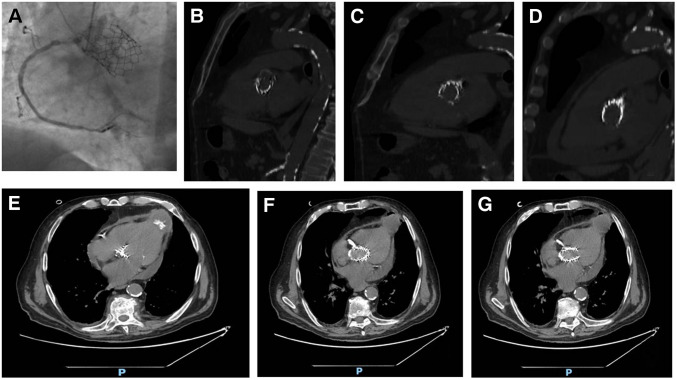

对症状性主动脉瓣狭窄的干预决策应权衡手术和经导管主动脉瓣植入术(TAVI)的风险。TAVI是一种成熟的技术,用于治疗老年和高危主动脉狭窄患者,采用多种不同的手术入路(逆行经股动脉、经腋窝、经主动脉或顺行经根尖入路)。经根尖入路需要心脏外科医生的参与,现在仅限于不能通过其他入路进行手术的病例。我们报告一例87岁的患者,患有严重外周动脉疾病,有经根尖入路TAVI病史,术后4年出现晕厥发作。影像学显示左心室顶动脉瘤,可能与先前的经根尖TAVI有关。该病例强调了在接受其他TAVI通路的患者中进行彻底的术前评估和长期随访的重要性,以及需要提高对罕见但重要的并发症(如心室假性动脉瘤)的认识。谨慎的患者选择和个性化的程序规划仍然是优化这一复杂人群结果的必要条件。

Decision-making for intervention in symptomatic aortic stenosis should balance the risks of surgery and of transcatheter aortic valve implantation (TAVI). TAVI is a well-established technique for treating elderly and high-risk patients with aortic stenosis using a variety of different surgical approaches (a retrograde transfemoral, transaxillary, transaortic or an antegrade transapical approach). The transapical approach requires the involvement of the heart surgeon and is now limited to cases where the procedure cannot be performed by alternative approaches. We report the case of an 87-year-old patient with severe peripheral arterial disease and a history of TAVI via transapical approach, who presented with a syncopal episode 4 years post-procedure. Imaging revealed a left ventricular apex aneurysm, likely related to the previous transapical TAVI. This case underscores the importance of thorough pre-procedural assessment and long-term follow-up in patients undergoing alternative TAVI access routes, as well as the need for heightened awareness of rare but significant complications such as ventricular pseudoaneurysm. Careful patient selection and individualized procedural planning remain essential to optimize outcomes in this complex population.